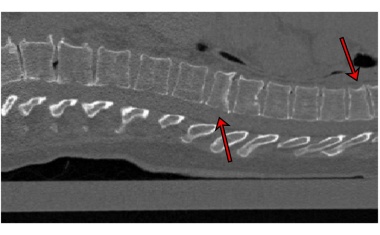

Forschende der Uni Kiel haben eine Software entwickelt, die Wirbelbrüche auf CT-Bildern automatisch erkennt und prognostisch bewertet.